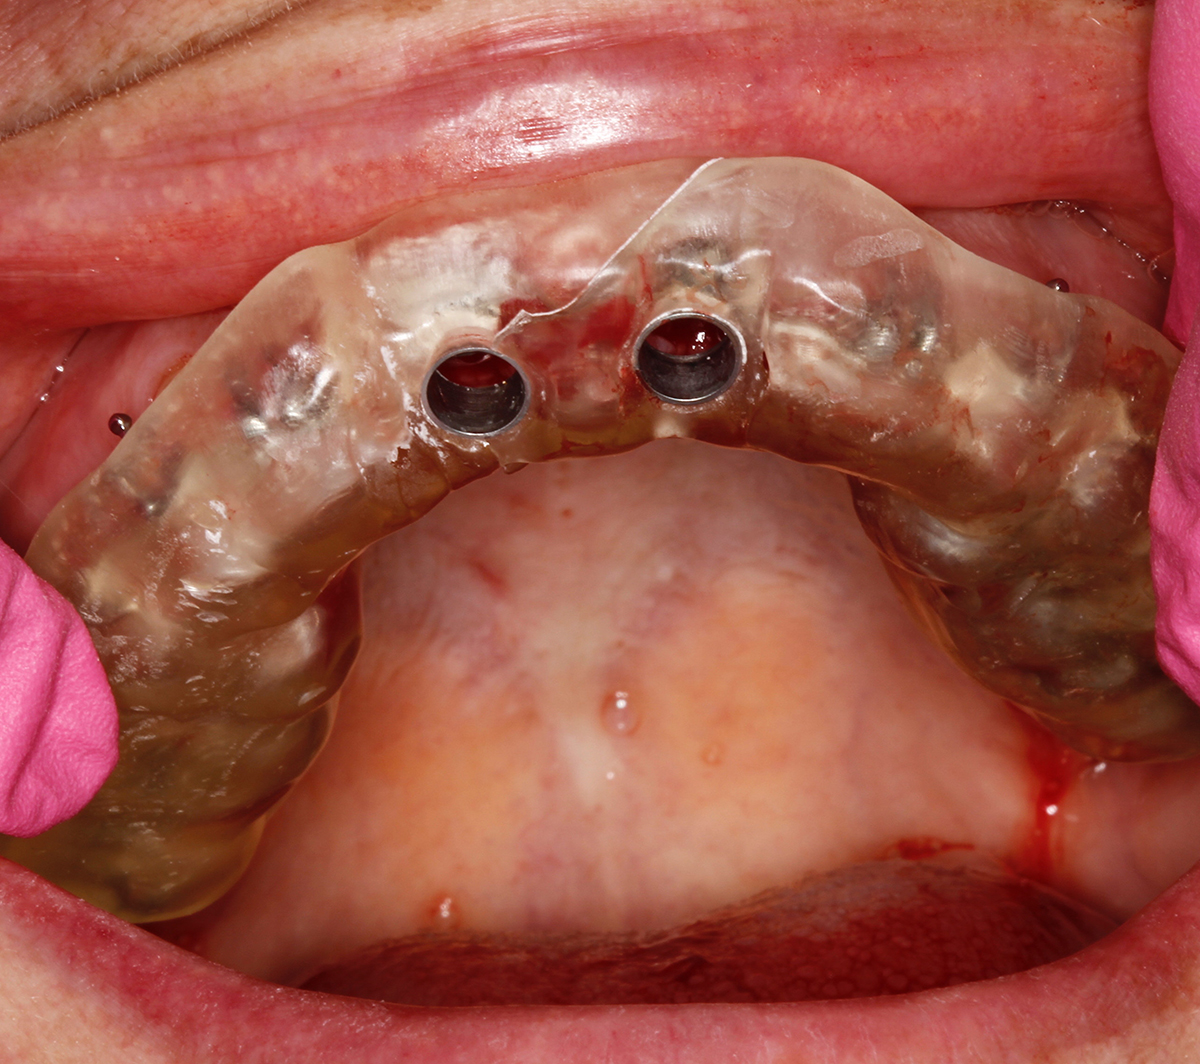

The special report presented below illustrates how orthodontic extrusion was successfully used to improve the periodontal architecture prior to the placement of two adjacent implants in the esthetic zone and thus allowed for a more ideal restorative result.